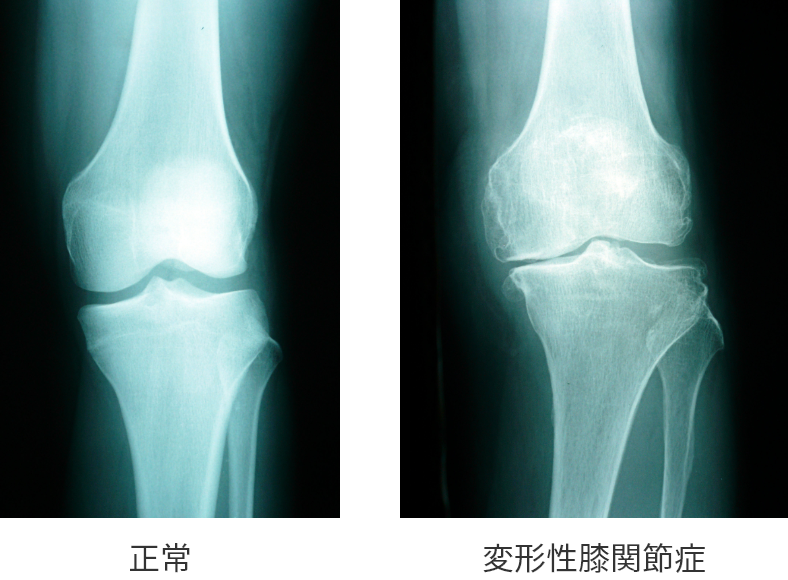

DISCRIPTION 変形性膝関節症とは

- 変形性膝関節症の病態

変形性膝関節症とは、膝関節の軟骨がすり減ることにより慢性炎症や変形が生じ、膝に痛みが生じる病気です。

この病気の原因には、膝の軟骨の表面が荒れてすり減り、それによって半月板が切れてしまうことが挙げられます。しかし反対に、先に半月板が切れてしまうことで膝にかかる衝撃を和らげるクッションの役割ができなくなり、結果として軟骨に障害が及ぶ場合もあります。

つまり、軟骨と半月板のどちらが先に痛むかは、人により異なります。